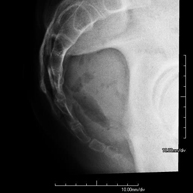

Tècnica que usa els raigs X a través de la qual s'obtenen imatges de l'interior de les extremitats per al seu estudi, especialment dels ossos. Indicacions: traumatisme, infeccions articulars. - RX Artrografia

Procediment que permet, mitjançant l'ús de raigs X, i després d'injectar un contrast a l'interior de l'articulació, detectar lesions d'aquestes articulacions (cartílag, os, tendons, etc. ) segons la distribució del contrast. - RX Pelvis